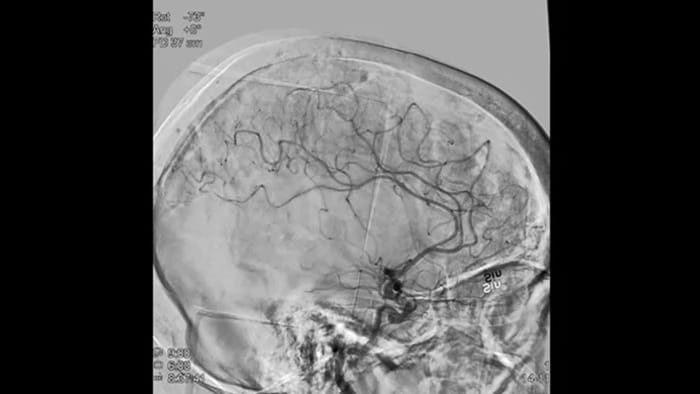

ClarityIQは、DSA撮影中の自動体動補正機能や、リアルタイム画像最適化処理により鮮明な画像を医師します。これにより、脳卒中治療において信頼性の高い画像での意思決定行うことができます。

高品質のDSA画像により、血栓が完全に回収されたかどうか、血栓の断片が脳内で遠位に分散しているかどうかを評価できます。また、ペナンブラへの血流の回復を確認し、治療前後の血流のチェックをすることができます。